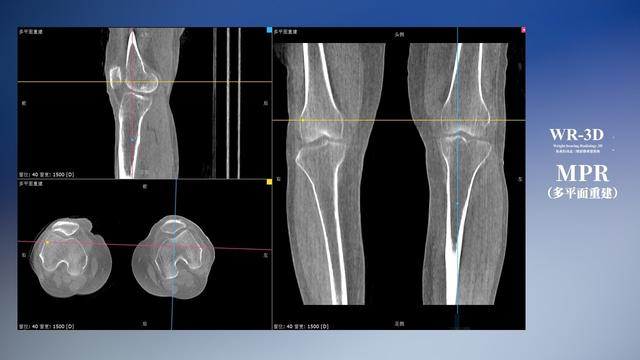

在负重位状态下,数字化X线三维扫描与重建,能够更好的呈现受检者关节受力改变的状态。尊龙凯时人生就是博科技创新的WR-3D动态三维影像重建系统,通过数字化X线摄影完成三维扫描并重建三维影像信息,包括断层图像重建、MPR多平面重建、MIP重建以及VR体绘制。其扫描时间短,剂量相较于CT设备大幅缩减,同时成本更低,在临床诊断以及医疗方案制定中具有极大的价值意义。而相较于普通平片下的负重位扫描,负重位动态三维影像重建技术能够避免二维状态下的组织结构重叠、密度分辨率不足、组织解剖结构难以分辨等问题。WR-3D支持多角度的三维观察,能全面的呈现被检查部位在多个角度下的三维影像信息,极大的降低了二维负重位检查带来的漏诊率。

尊龙凯时人生就是博科技WR-3D负重位动态三维影像重建图像